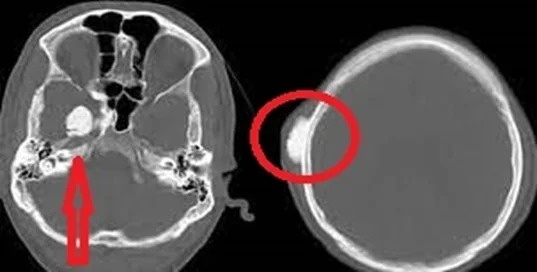

В большинстве случаев остеома протекает без каких-либо симптомов. Человек может самостоятельно обнаружить у себя нарост, внутренние опухоли находят при обследованиях на рентгенографии, КТ, МРТ. Иногда остеома расположена близко от нервных окончаний, поверхности кожи, может блокировать анатомические проходы, вызывать дискомфорт.

• рентгенография, КТ, МРТ – один или два панорамных снимка. Лучше отдать предпочтение современным аппаратам компьютерной диагностики;

Очень важно, чтобы все справки были оформлены в соответствии с нормативами Минздрава, имели точные формулировки диагноза (с указанием кода МКБ), классификации, назначений. Ключевым аспектом в диагностике костных патологий выступают рентгенографические снимки, поскольку они позволяют установить размер и локацию остеоида. Если опухоль сдавливает соседние ткани, лучше сделать МРТ: она покажет более детальную картину.